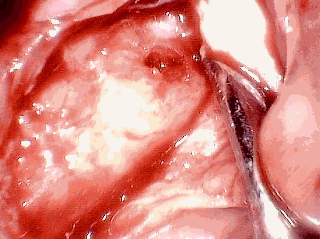

These next two images are my own surgery pictures. The first picture is with the gum retracted. You can see small holes in the bone. That is diseased bone. The second picture is with top cut off the bone. You can see there is just a giant hole that extends back into my jaw. I was actually awake during the surgery, and made sure my dentist took those pictures, specifically for this website.